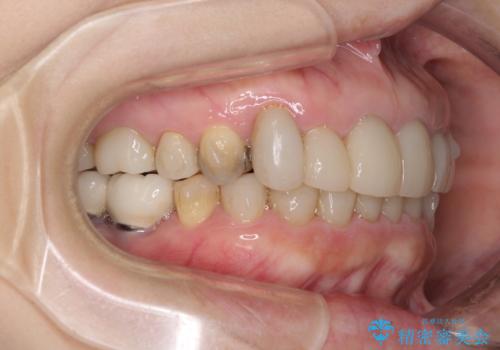

- 下顎の前歯に激痛を覚えて来院された患者様です。

取り急ぎ下顎前歯数歯の根管治療を、銀座しらゆり歯科医院長の林先生にお願いし、それ以外に気になっている、不自然な色調のクラウン、金属部分が見えてブラッシングがしにくいインプラント補綴、口元の突出感、出血のしやすい歯周ポケットなど、全てを解決するための治療を行うこととしました。

期間と費用はかかりましたが、気になっていた部分全てを改善でき、患者様には大変満足していただきました。